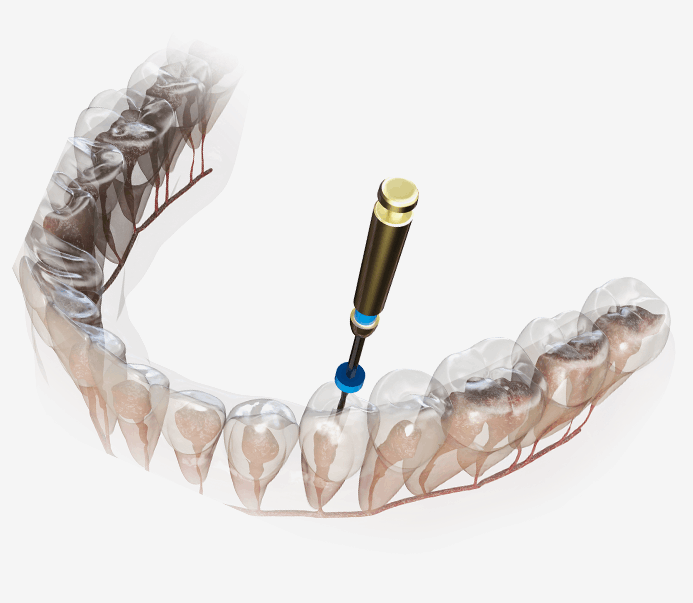

신경치료

신경치료는 개인마다 신경관의 개수와 형태가

모두 다르기 때문에 문제를 일으킨 신경관을 모두

찾아내는 것이 관건입니다.

신경치료는 충치가 신경까지 번진 경우, 치아가 부러져 신경이 노출된 경우, 뿌리에 염증이 생긴 경우 진행하는 치료방법입니다. 신경관이 막혀있거나 신경관에 post가 박혀있는 경우 치료의 난이도는 매우 어려워 지며 많은 분들이 발치를 권유 받습니다. 청담뷰치과는 자연치아살리기 진료를 전문적으로 다뤄왔기에 막힌 신경관을 찾거나 만곡이 심한 신경관을 다루는 치료까지 성공적인 결과를 제공해 드릴 수 있습니다.